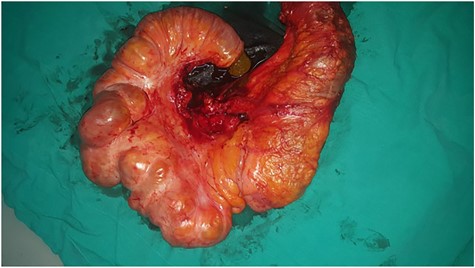

Initially, conservative therapy with nasogastric decompression, intravenous fluids and monitoring was applied. Twelve hours later, symptoms of bowel obstruction persisted, WBC count elevated to 14 000 and peritoneal effusion increased to 400 ml on ultrasonography. Consequently, we performed an exploratory laparotomy, which showed a mass involving the distal ileum and small bowel dilation proximal to the obstruction (Figs. 1 and 2). The terminal ileum was resected with right hemicolectomy and primary ileocolic end-to-side anastomosis was performed using simple interrupted suture (vicryl suture 2-0) (Fig. 3).

(1) Dilated small intestine proximal to the obstruction and (2) a 20 cm ileal mass.